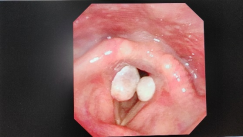

声带肉芽肿是一种良性的声带肿瘤,通常由声带的慢性刺激、损伤或炎症引起。肉芽肿常呈现为小而红色或棕色的肿块,主要位于声带的边缘或中间部分。其形成的原因可能包括过度使用嗓音、胃酸反流、吸烟或过敏等。

声带肉芽肿